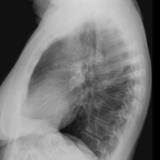

Case 3 Lat only

Peric calcification

Date: 03/17/2004

Views: 8419